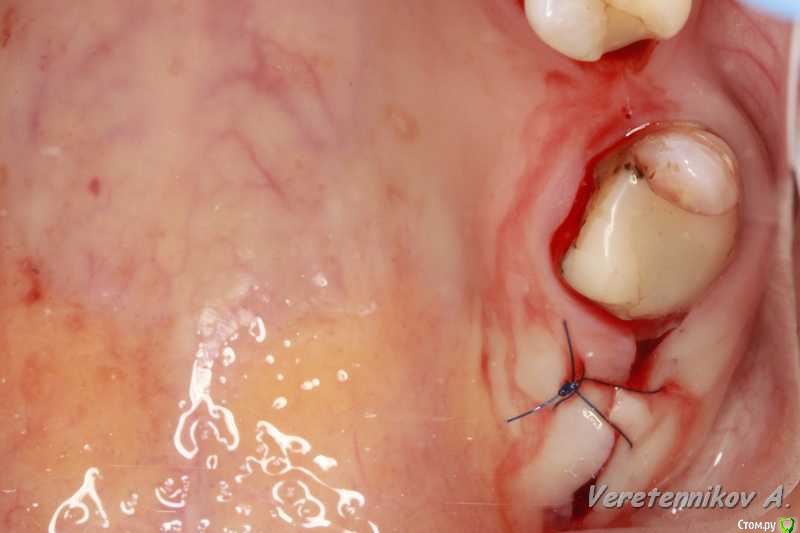

an_ver Опубликовано 16 января, 2016 Автор Поделиться Опубликовано 16 января, 2016 Клёво!!!Можно вопрос: как сст всовывали ?Просто опыта в этом аспекте очень мало и понятие "в щели" не совсем понятно.СпасибоВ щели: это свободные обьем лунки,после установки импланта,т.е. все пустоту забиваем графтом (Апатос). По ССТ: скальпель 15С, параллельно кости осторожно,маятниковыми движениями,до уровня прикрепления или глубже формируете карман,вкол с вестибулярки-выкол в лунке,вкол в сст,выкол там же,далее вкол внутри кармана и затягиваете сст...но проще посмотреть...сейчас А.Смолякова по рецессии выложила видео,принцип такой же 2 Ссылка на комментарий

an_ver Опубликовано 16 января, 2016 Автор Поделиться Опубликовано 16 января, 2016 перфо не заметил,но понял теперь почему так глубоко сст!ждем динамики!Перфо-второй шов,ниже Ссылка на комментарий